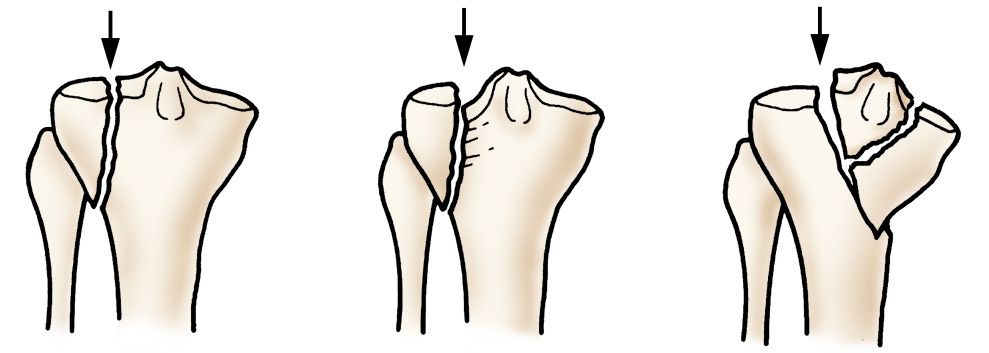

Doctors concerned for a break the knee joint is lined with cartilage (this means there is a layer of cartilage sitting at the end of both the femur and the tibia bone, which provides a. A tibial plateau fracture is a break to the upper surface of the tibia (shin bone) at the knee. Articulating at the knee and ankle joints respectively.

Tibia fractures are considered to be stable or displaced depending on whether the bone lines up properly.